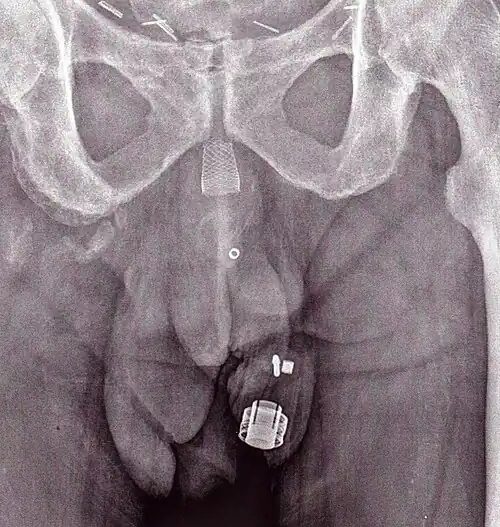

Artificial urinary sphincters (left to right: AMS 800 and ZSI 375)

Frederic Foley was the first to describe an externally worn artificial urinary sphincter to treat urinary incontinence, published in 1947.[5] In 1972, F. Brantley Scott and colleagues from Baylor College of Medicine designed the first precursor of contemporary artificial urinary sphincter.[6][7] The first AUS model on the market was the AMS 800 (Boston Scientific, Marlborough, MA), developed 50 years ago.[8][9] It is a 3-component device with a cuff placed around the urethra, a pump inserted in the scrotum and a pressure generating reservoir placed in the pelvis, which comes as a kit to prepare and to fill up before implantation.[10]

Another AUS model is the ZSI 375 (Zephyr Surgical Implants, Geneva, Switzerland), introduced in 2008.[11] It is a one-piece two-part device with a cuff and a pump unit with an integrated spring; it comes in one piece, pre-connected and pre-filled.[1][12] There is no abdominal component in the ZSI 375, which along with its ready-to-implant configuration reduces the operating time.[13] Furthermore, because there is no abdominal component, surgical interventions in the retroperitoneal space are not required. Previous surgeries, such as radical prostatectomy, may lead to post-operative scarring and fibrosis in the retroperitoneal space. Thus, avoiding dissection of retroperitoneal tissues avoids risks of surgical complications.[14][15] Another advantage of the ZSI 375 model is the possibility to increase or decrease the pressure inside the device after implantation to meet the desired continence rate and satisfaction of the patient. These adjustments particularly help to control continence in cases of post-implantation urethral atrophy or urinary retention (poor urine flow).[16][17][13] Adjustment of the pressure can be done in an outpatient setting by adding or removing sterile saline solution via a syringe through the scrotum.[12] By 2019, more than 4,500 ZSI 375 artificial urinary sphincters have been implanted worldwide.[11] In addition to the devices mentioned above, new devices are being brought to market, such as the Rigicon ContiClassic and ContiReflex Artificial Urinary Sphincter systems. [18][19]